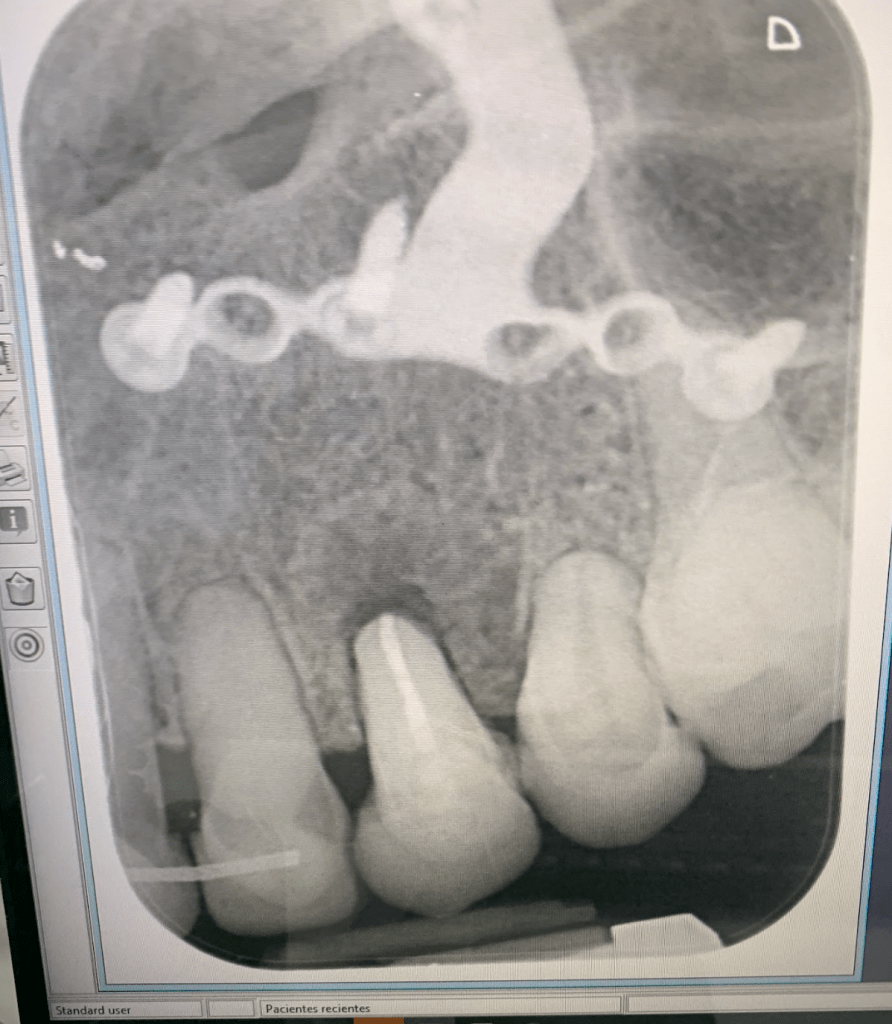

Vertical root fracture